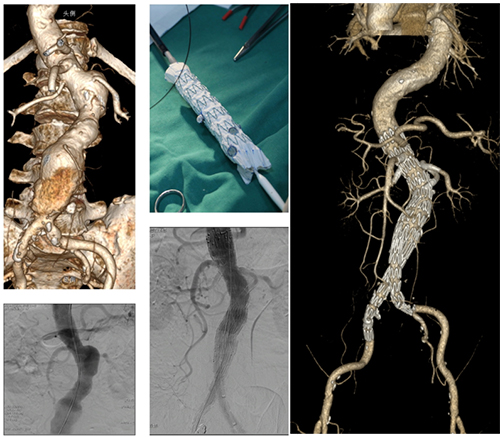

手术在全麻下实施,根据术前CT测量数据转化为平面图,根据图纸改制支架开窗并缝制短分支后,经双侧股动脉、左腋动脉入路植入体内过程顺利,术毕造影可见瘤体隔绝满意,分支动脉血流通畅(如下图示)。术后腰腹痛症状缓解,术后第4天顺利出院。随访3年期间瘤体逐渐缩小,无明显内漏,无感染复发。

手术过程图示:根据术前CT数据转化成平面图,台上改制支架并植入体内隔绝瘤体并重建脏动脉分支血流;术后复查可见瘤体逐渐缩小,支架形态良好,分支血流通畅

省立医院血管外科在吴学君主任带领下,由董典宁副主任医师牵头成功申报医院新技术项目,举全科之力,逐步开展并改进创新了台上改制开窗-分支支架技术,形成了强有力技术团队,具备了急诊手术改制开窗-分支支架的能力,大幅度缩短了术前的准备时间,有效解决了高危高龄的复杂胸腹主动脉疾病的腔内微创治疗问题。团队至今共完成40余例多内脏动脉分支重建,取得了满意疗效,围手术期手术并发症可控,随访期间可见主动脉分支通畅率高,瘤体封闭满意。

改制开窗-分支支架治疗肾周腹主动脉瘤,重建内脏动脉4分支,分支动脉血流通畅,瘤体封闭满意

改制开窗-分支支架治疗白塞氏病相关的内脏动脉区囊性动脉瘤,随访期间可见内脏动脉分支通畅,瘤体逐渐消失

急诊行改制开窗-分支支架治疗破口位于内脏动脉区的复杂性B型主动脉夹层,重建4个内脏动脉分支,术后顽固性胸腹部疼痛消失,分支动脉血流通畅